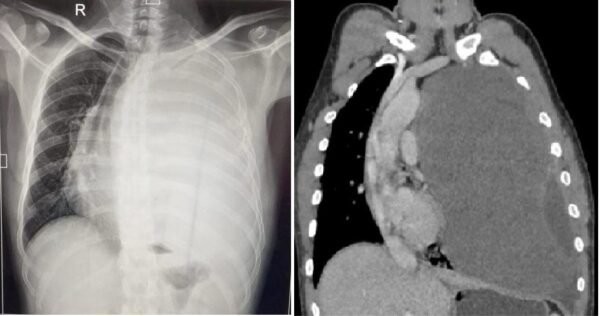

विक्रम सिंह को छाती में दर्द की समस्या जुलाई 2023 में शुरू हुई थी। लगभग एक साल से वह छाती में होने वाले तीब्र दर्द से परेशान थे। आस-पास के अस्पतालों से लेकर उन्होंने राज्य के अन्य बड़े अस्पतालों में भी अपनी बीमारी का परीक्षण कराया। थोरेसिक सर्जन उपलब्ध नहीं होने की वजह से जब कई अस्पतालों ने हाथ खड़े कर दिए तो विक्रम की अन्तिम उम्मीद ऋषिकेश एम्स पर आकर टिक गई। पिछले महीने एम्स पहुंचने पर विक्रम ने सीटीवीएस विभाग के चिकित्सकों को अपनी समस्या से अवगत कराया। सीटी स्कैन कराने पर डॉक्टरों ने जब रिपोर्ट देखी तो पता चला कि मरीज के बाएं फेफड़े पर एक विशालकाय ट्यूमर बन गया है, जो उस फेफड़े को पूरी तरह दबाने के साथ-साथ कभी भी दाएं फेफड़े को भी अपनी चपेट में ले सकता था।

एम्स के हृदय छाती एवं रक्त-वाहिनी शल्य चिकित्सा (सी.टी.वी.एस.) विभागाध्यक्ष डॉ. अंशुमान दरबारी ने बताया कि हाई रिस्क में होने के बाद भी ट्यूमर निकालने के लिए ओपन सर्जरी करने का निर्णय लिया गया। डॉ. दरबारी ने बताया कि बीती 11 जून को उनकी कुशल टीम ने सर्जरी द्वारा मरीज की छाती खोलकर एक ही बार में पूरा ट्यूमर निकाल दिया। सर्जरी करने वाली टीम में डॉक्टर दरबारी के अलावा सीटीवीएस विभाग के डॉक्टर अविनाश प्रकाश और एनेस्थेसिया विभाग के डॉ. अजय कुमार का विशेष योगदान रहा। ग्रसित मरीज की छाती से निकाला गया ट्यूमर 22×20 सेमी. और 3.2 किलोग्राम वजन का है।